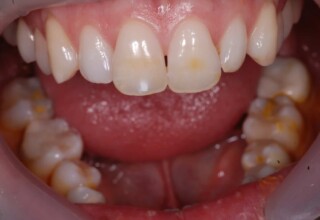

Dark root canal teeth

A rare case of dark root canal teeth with additional external absorption on the central incisor. After removal of the affected tissues of the central incisor, the tooth could not be directly bleached because of the soft tissue contact. The tooth was initially restored to provide the original tooth form, then it was bleached and the restoration was finalized.